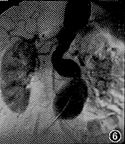

图1,2 图1为SE左前斜位,示主动脉弓部囊状突出,内无信号;图2为三维增强磁共振血管造影(3D DCE MRA)左前斜位,示左锁骨下动脉开口以远可见囊状突出,其内信号与主动脉弓相同,手术证实为假性动脉瘤 图3,4 图3为3D DCE MRA冠状位,示腹主动脉扭曲,肾动脉水平以下瘤样扩张,左肾动脉起始部局限性重度狭窄,双侧髂总动脉多发狭窄和扩张;图4 为SE轴位,示腹主动脉扩张,其内可见新月形附壁血栓,手术证实为真性动脉瘤伴附壁血栓 图5,6 图5为数字减影动脉血管造影(IADSA)冠状位,示腹主动脉扭曲延长,双肾动脉水平以下呈囊状扩张,左肾动脉起始部局限性重度狭窄,右肾动脉起始部局限性轻度狭窄;图6为3D DCE MRA冠状位,除与图5相同表现外,还可见双侧髂总动脉、髂内、外动脉多发狭窄伴扩张,管腔不规则 图7,8 图7为3D DCE MRA冠状位,示双侧髂总动脉及髂内、外动脉多发狭窄,右侧桥血管通畅,与髂总动脉吻合处轻度狭窄;图8为IADSA冠状位,除与图7相同表现外,侧支血管显示较3D DCE MRA佳

病变组34例 3D DCE MRA与IADSA或(和)手术结果对照,符合率分别为胸腹主动脉100.0%(12/12例) (图1~6),髂动脉87.5%(7/8例)(图7,8),颈动脉80.0%(4/5例),头臂动脉75.0%(3/4例),肾动脉60.0%(3/5例),总的符合率为85.3%,主动脉及其主支病变则分别为100.0%和77.3%。与IADSA或(和)手术结果对照的34例病人3D DCE MRA显示假阴性2例,16例正常组中假阳性2例,误诊率8.0%;其敏感性、特异性和准确性分别为94.1%、87.5%和92.0%。

因TOF法的空间分辨率低和饱和效应,以及相位对比法因肾动脉开口处湍流,易误为轻度狭窄等缺点,影响非增强MRA对肾动脉狭窄判断的准确性。3D DCE MRA 与血流方向无直接关系,与靶血管的对比剂浓度有关,正确估算延迟时间,能显示肾动脉主干以及部分副肾动脉和肾内动脉分支,较正确地显示病变部位和程度。本组5例肾动脉狭窄3D DCE MRA ,与手术或(和)IADSA符合者3例,1例因延迟时间估算有误导致假阴性,另1例为病变程度高估。2D TOF 技术对下肢血管成像已取得较好效果,而对髂动脉病变的判定,尚有难度。3D DCE MRA能较清晰地显示髂总动脉、髂外动脉、髂内动脉主干和部分分支。本组8例与IADSA或(和)手术符合者7例,1例将右侧髂总动脉重度狭窄误为闭塞。另外对髂内动脉分支及侧支血管的显示不如IADSA(图7,8)。这可能与层厚和选择不当有关。因此,3D DCE MRA判断主动脉主支病变,如肾动脉等仍有假阳性和病变程度高估现象,与IADSA尚有一定的差距,除正确估算延迟时间外,选用合适的成像参数,特别是层厚和矩阵,也是至关重要的[12,13]。